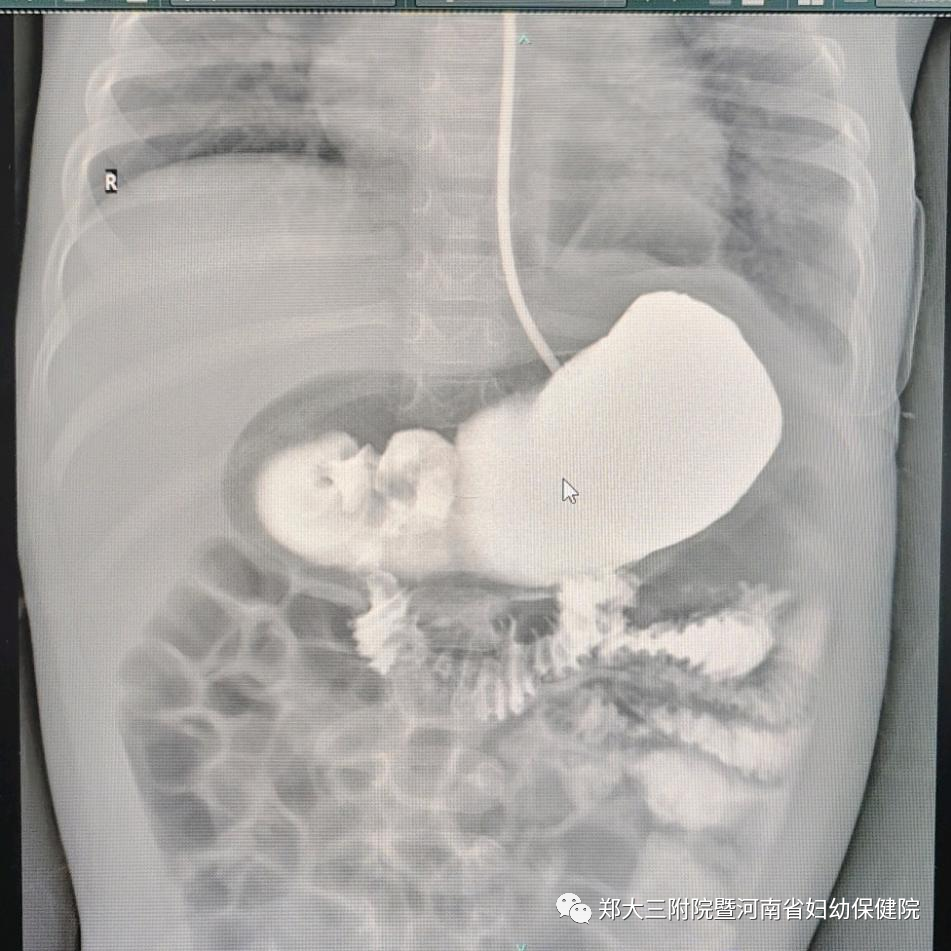

术后胸腹 X 线片提示恢复良好。

术后消化道造影提示胃体恢复至正常位置。